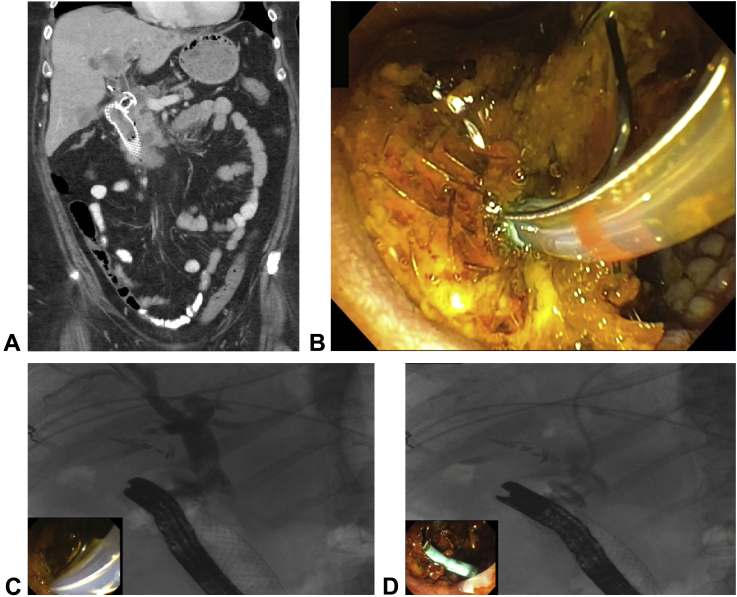

A 58-year-old woman with a history of stage IV pancreatic adenocarcinoma, who had received a 10-mm × 10-mm lumen-apposing metal stent (LAMS; Boston Scientific, Marlborough, Mass) choledochoduodenostomy and a 22-mm × 60-mm duodenal stent (Boston Scientific) for biliary ductal obstruction and gastric outlet obstruction presented with obstructive jaundice and symptoms including epigastric pain, nausea, and vomiting. A CT scan revealed enlarged liver metastases and increased left biliary dilation (Fig. 1A). We chose to endoscopically stent the left biliary obstruction through the pre-existing LAMS placed 3 months prior (Video 1, available online at www.VideoGIE.org).

A, CT scan showing the duodenal stent at the far left and the adjacent choledochoduodenostomy lumen-apposing metal stent (LAMS). Immediately superior to the short-axis LAMS is biliary dilation that extends deep into the liver. B, Endoscopic view of the sphinctertome between the LAMS on the left and the duodenal stent at the right with its phalanges protruding toward the endoscope. The LAMS was filled with debris. C, Fluoroscopic view illustrating dilation of the proximal biliary duct and lack of contrast medium in the left biliary system. D, Fluoroscopic view of placement of a biliary stent through the LAMS and into the strictured left biliary branch.

Using a side-viewing 41.1F endoscope (TJF-Q180V, Olympus America, Chelmsform, Mass), we visualized the choledochoduodenostomy occluded with debris (Fig. 1B). A 39-mm sphinctertome (Boston Scientific) was passed through the LAMS, and contrast medium showed a stricture at the branch of the left biliary system and upstream dilation (Fig. 1C). A 0.025-inch guidewire was advanced into the left biliary system, followed by a straight 7F × 9 cm stent (Olympus America) placed across the stricture with complete drainage of the biliary tree (Figs. 1C and D). A plastic biliary stent was chosen because of its easier maneuverability compared with the rigidity of the metal stent catheter. A metal biliary stent with a larger diameter would occlude or block the contralateral biliary system.